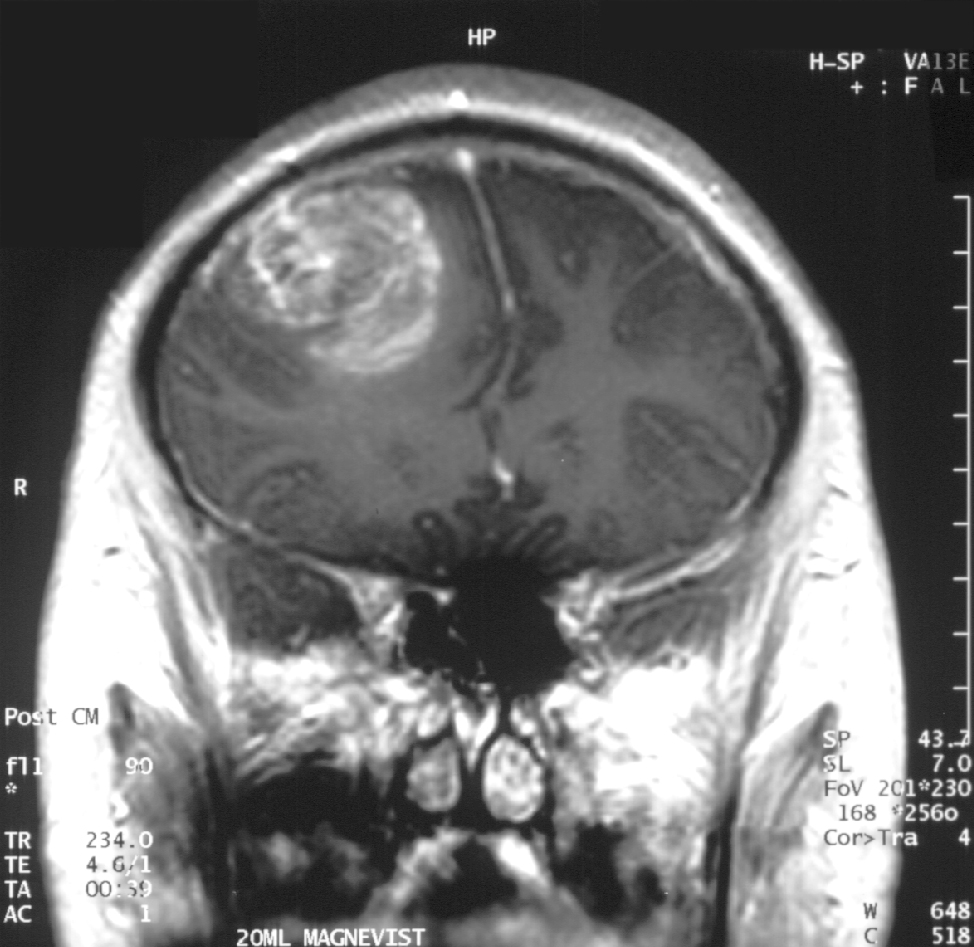

Immagine, glioblastoma (astrocitoma) OMS di IV grado – RMR vista coronale, post contrasto. Ragazzo di 15 anni. Credito: Christaras A / Wikipedia.